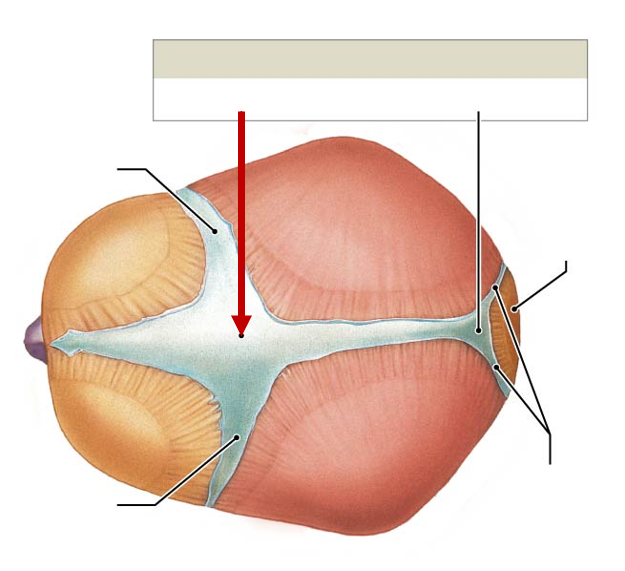

Sella turcica

Middle of sphenoid bone, in body